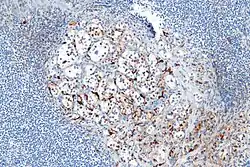

Micrograph highlighting the sustentacular cells in a paraganglioma. S100 immunostain